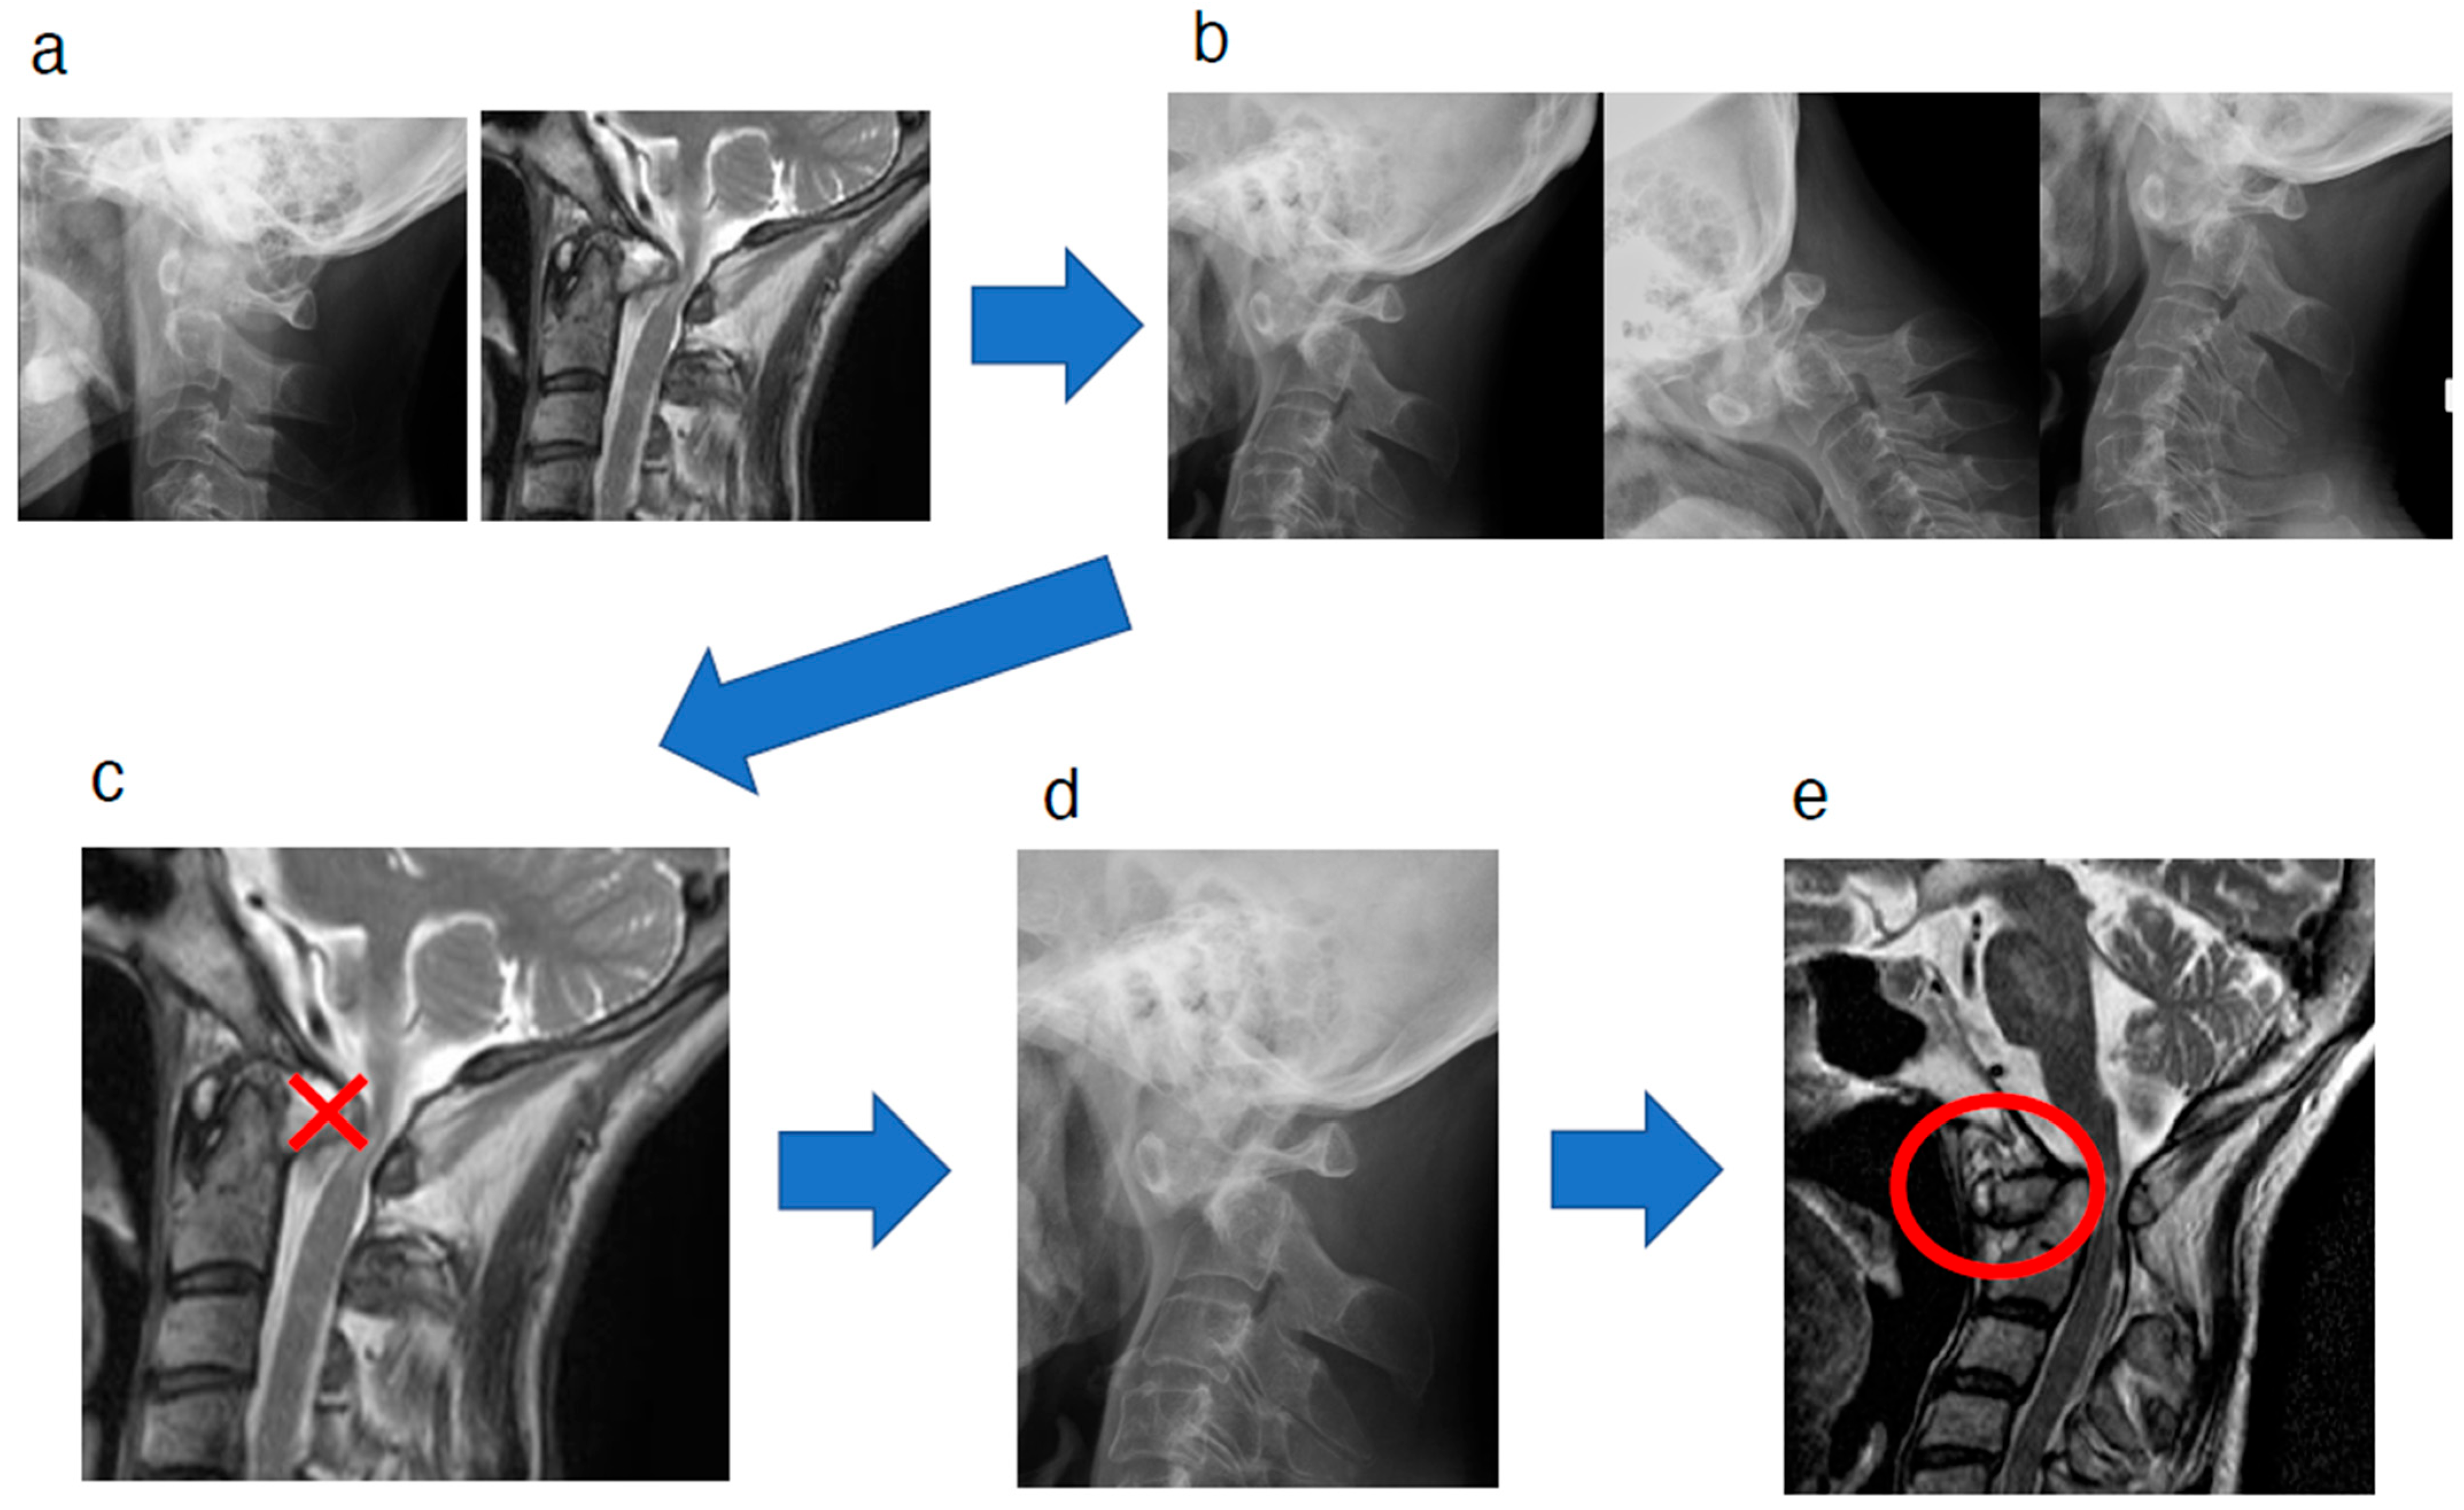

2. Case Presentation

3. Discussion